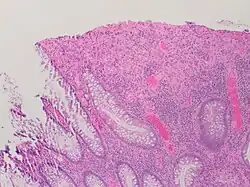

| A micrograph demonstrating cryptitis, a microscopic correlate of colitis. H&E stain. | |

An important investigation in the assessment of colitis is biopsy for histopathology. A very small piece of tissue (usually about 2mm) is removed from the bowel mucosa during endoscopy and examined under the microscope by a histopathologist. A biopsy report generally does not state the diagnosis, but should state any presence of chronic colitis, give an indication of disease activity, as well as state the presence of any epithelial damage (erosions and ulcerations).[6]

Histopathology findings generally associated with chronic colitis include:[6]

-

Crypt degeneration -

Crypt branching and other architectural distortions -

Paneth cell (pictured) or gastric metaplasia (only applies in the left colon and rectum)

Other findings include basal plasmacytosis and mucin depletion.[6] Histopathology findings generally associated with active colitis include:[6]

Neutrophilic cryptitis (neutrophils within crypt epithelium) -

Crypt abscesses (luminal neutrophilic aggregates) -

Gland destruction -

Ulceration (seen here as absence of epithelium, and granulation tissue with many fibroblasts)